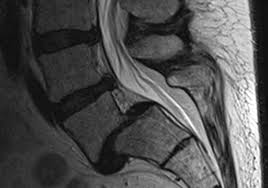

La nueva resonancia muestra esta enorme listesis o luxacion de S1 sobre S2, y cuya terapia se hace difícil sobre todo en un paciente con escasas molestias.

Lo unico que puede pensarse en una anomalía de transición donde existia una listesis y al quitar el disco

S1 – S2, se ha resbalado ambos segmentos hasta llegar a la topsis del sacro.

ESPONDILOLISTESIS. TOPSIS SACRA